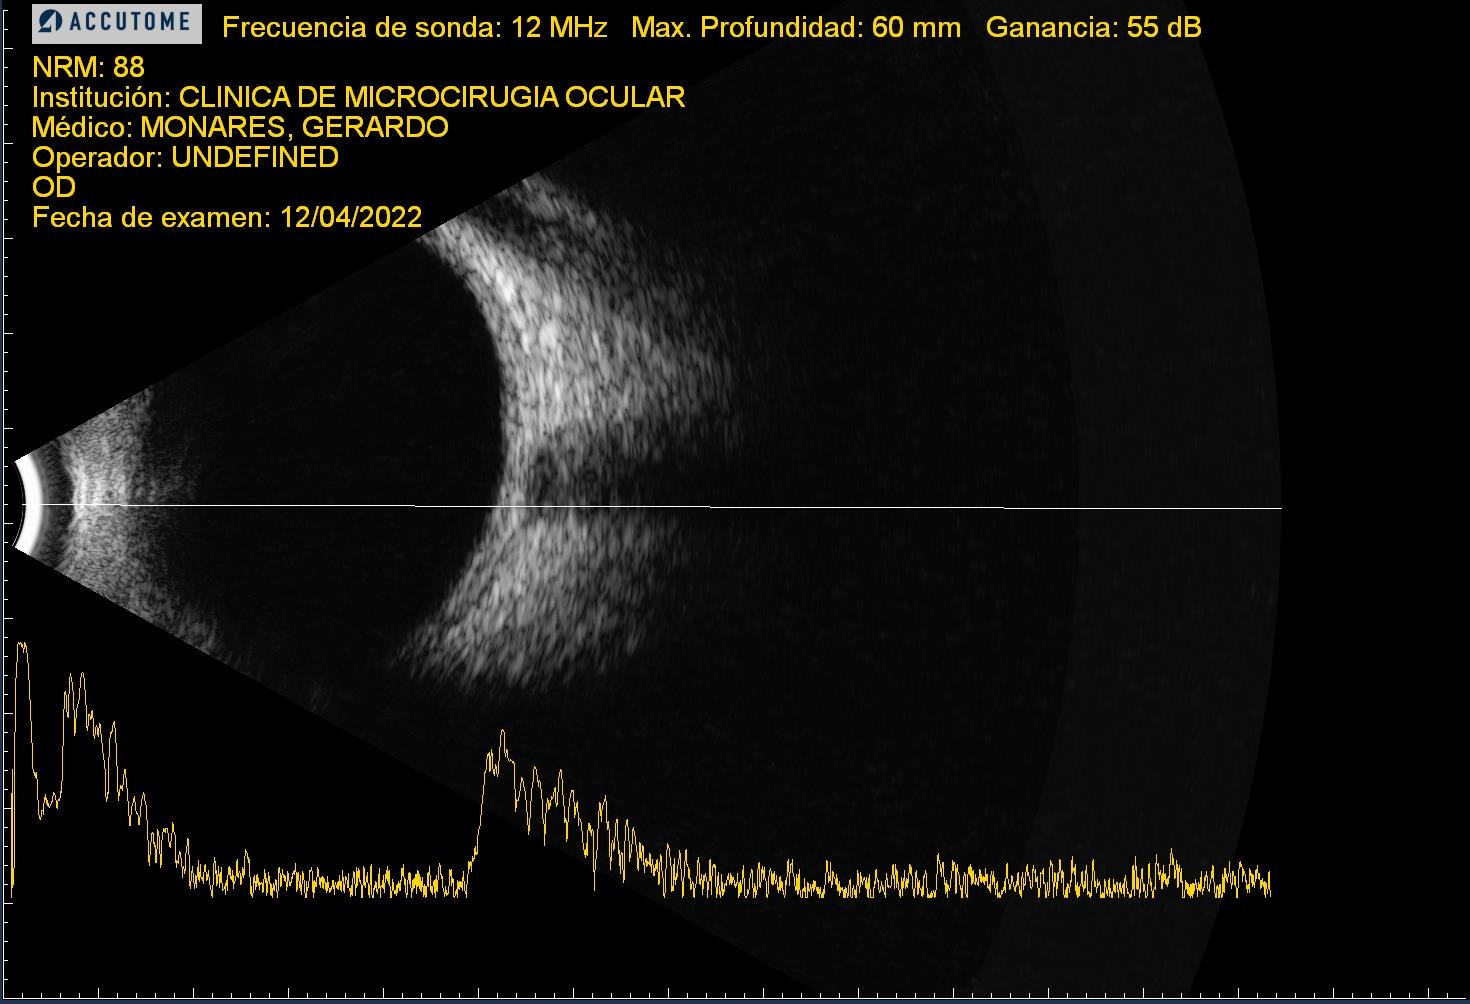

| RDP HV o HS | ![]() ![]() ![]() | ![]() ![]() ![]() | Normal o EMD | Normal o engrosamiento coroideo | ![]() | CIRUGIA: Vitrectomía + Endolaser | H Vítrea H Subhialoidea |

| RDP DRT | ![]() | ![]() | ![]() | ![]() | CIRUGIA: Vitrectomía + Endolaser + Silicón | Tracción sobre todo macular | |